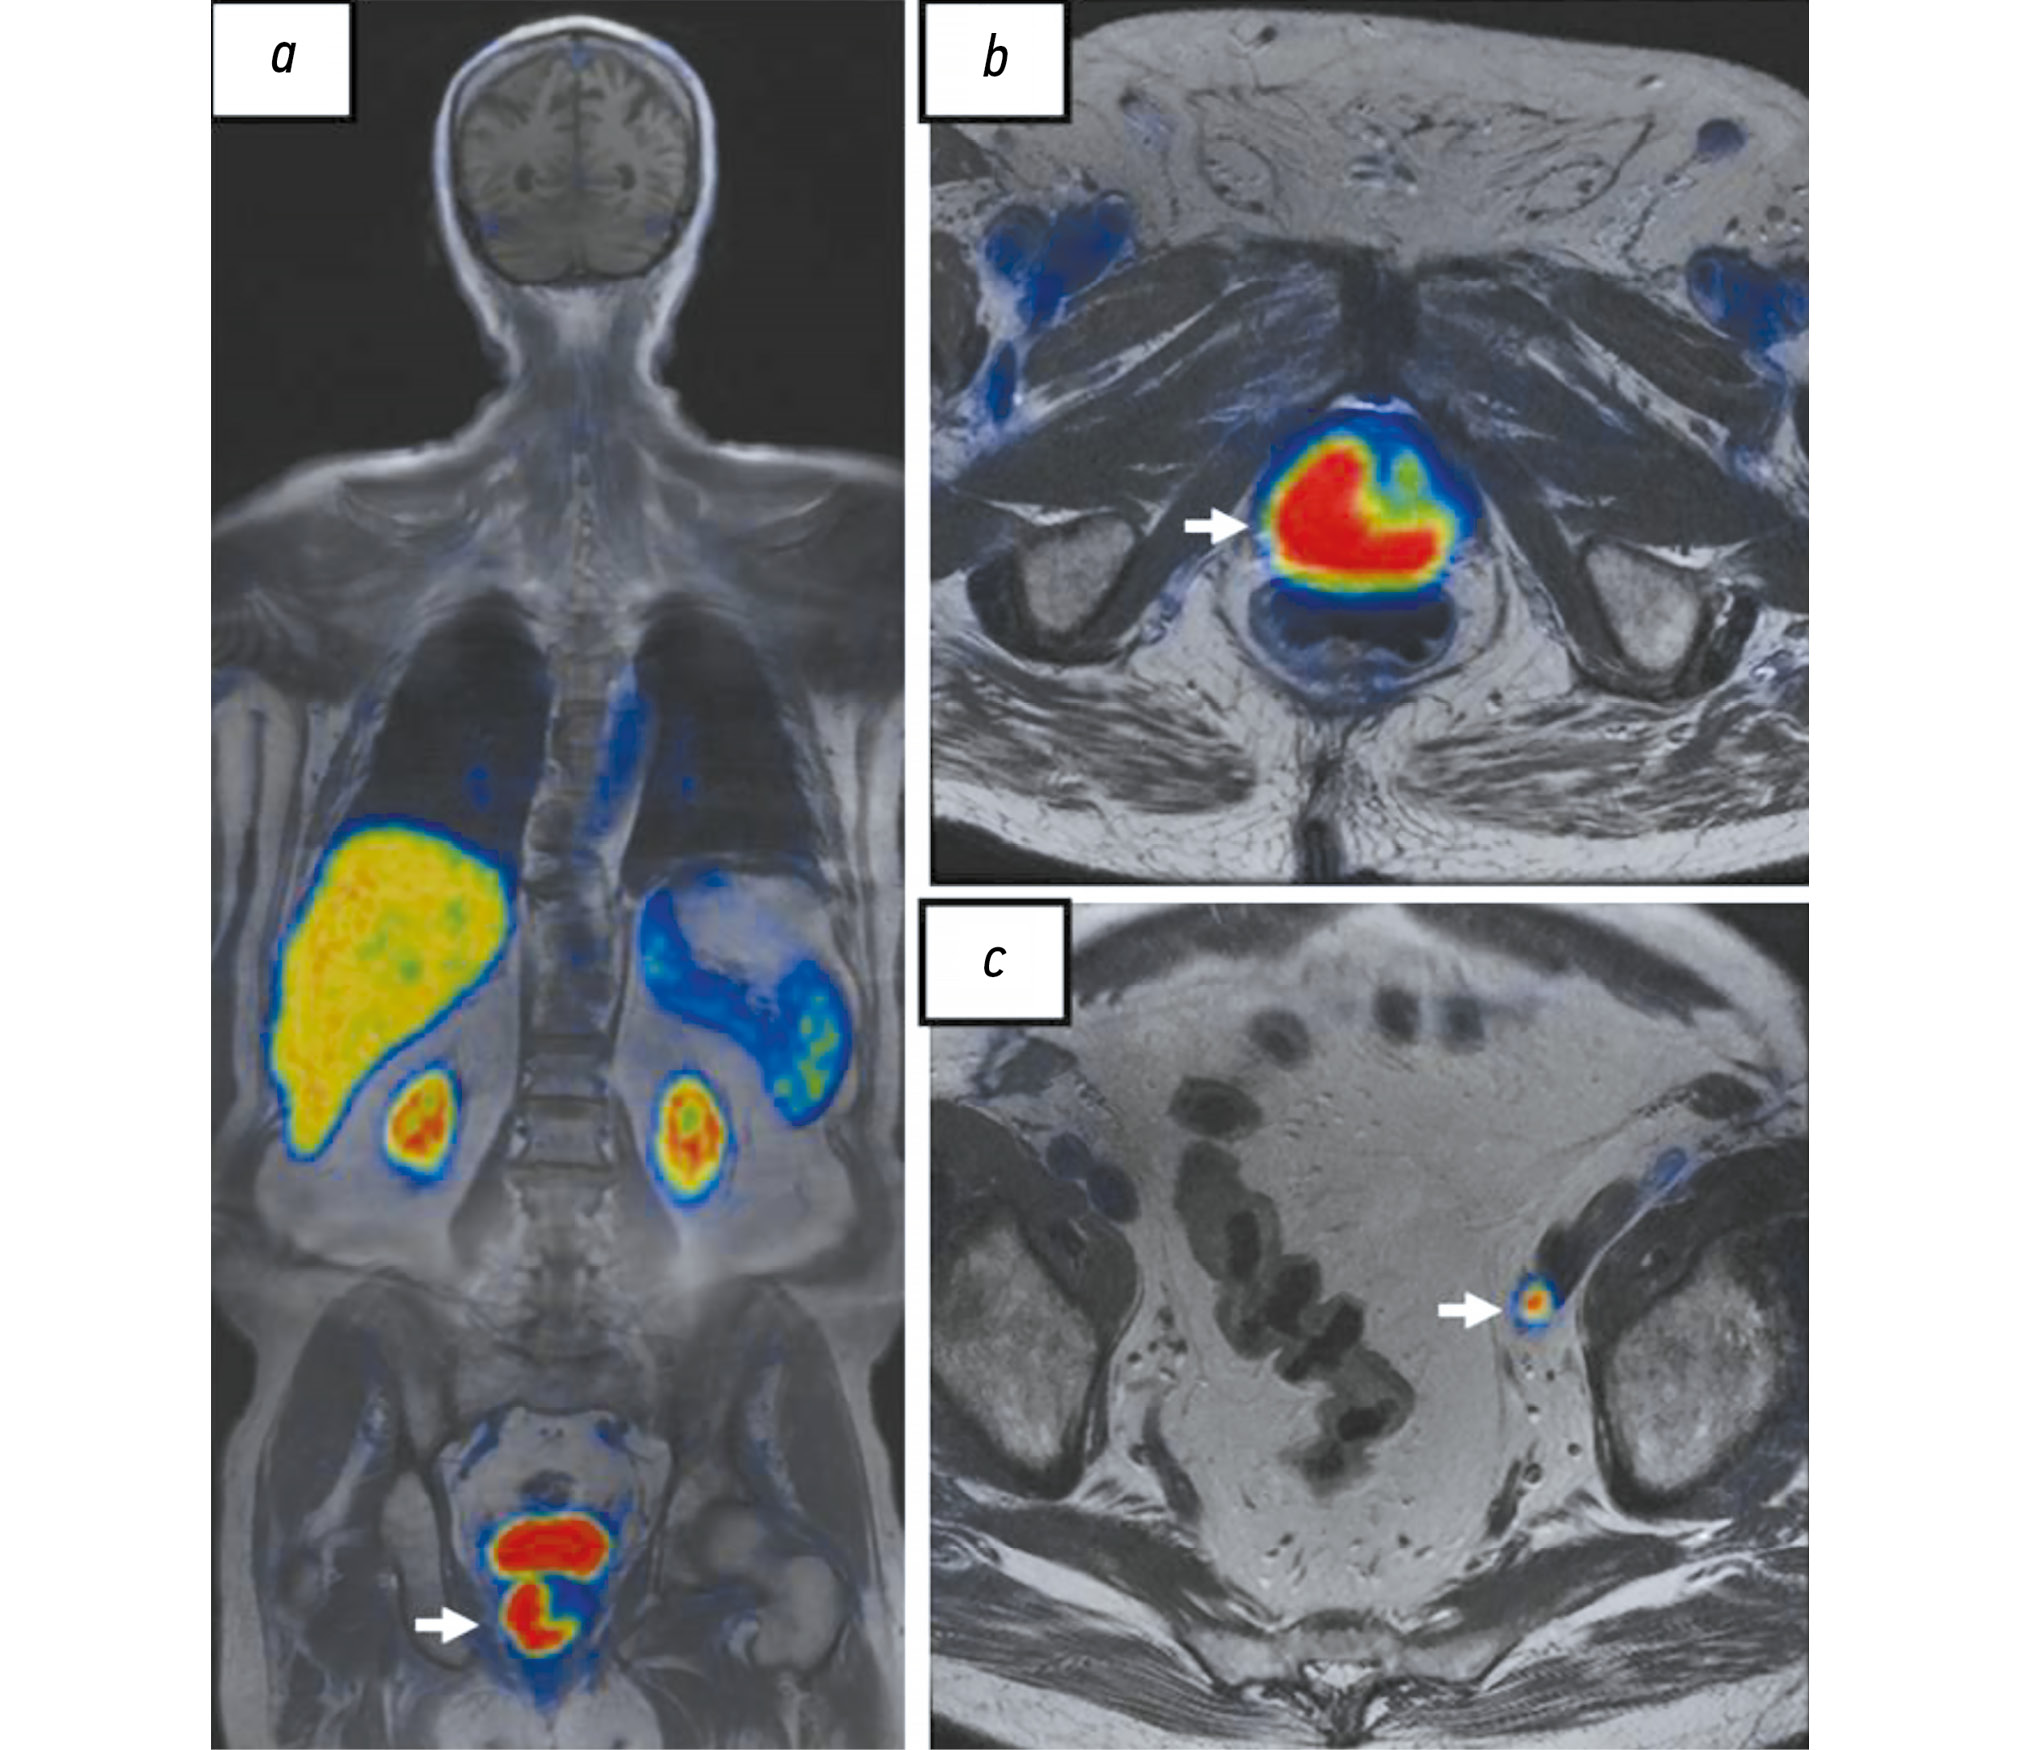

ПСМА представляет собой трансмембранный гликопротеин, выделенный из клеток РПЖ в 1987 году. Его низкую экспрессию определяют в мембранах нормальных эпителиальных клеток предстательной железы и её гиперплазированной ткани. Экспрессия ПСМА повышена на мембранах клеток РПЖ в 90% случаев [52] и наиболее выражена при его агрессивном кастрационно-резистентном типе, местном рецидиве и метастазах (рис. 3). Кроме того, повышение его экспрессии периодически наблюдают в эндотелии солидных опухолей других локализаций, ассоциированных с неоангиогенезом [53].

Рис. 3. Результаты совмещённой позитронно-эмиссионной и магнитно-резонансной томографии c 18F-простатоспецифичным мембранным антигеном-1007 всего тела, собственное наблюдение: a, b — опухоль предстательной железы с субтотальным вовлечением её правой половины с распространением на левые отделы (стрелки); c — гиперэкспрессия 18F-простатоспецифичного мембранного антигена-1007 в метастазе рака предстательной железы в подвздошном лимфатическом узле (стрелка).